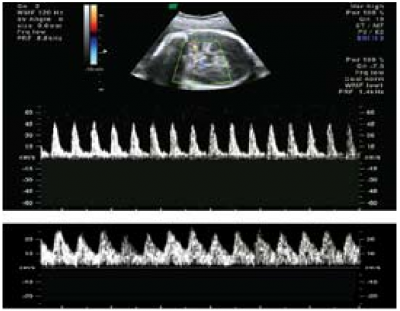

מבנה כיסתי (Cystic) מוחי בקו האמצע עם מדגם זרימה מערבולית (Turbulent flow), מלווה בירידת תנגודת כלי דם במוח, טיפוסי למום זה (תמונה 4). מפרצת (Aneurysm) של וריד גאלן יכולה להביא לאי ספיקת לב והידרופס עוברי (Hydrops fetalis) יחד עם נזק מוחי מקומי של התרככות (Encephalomalacia). דופלר צבע ותלת ממדי מסייעים בהגדרת מבנה כלי הדם והאזור המוחי הפגוע[34].